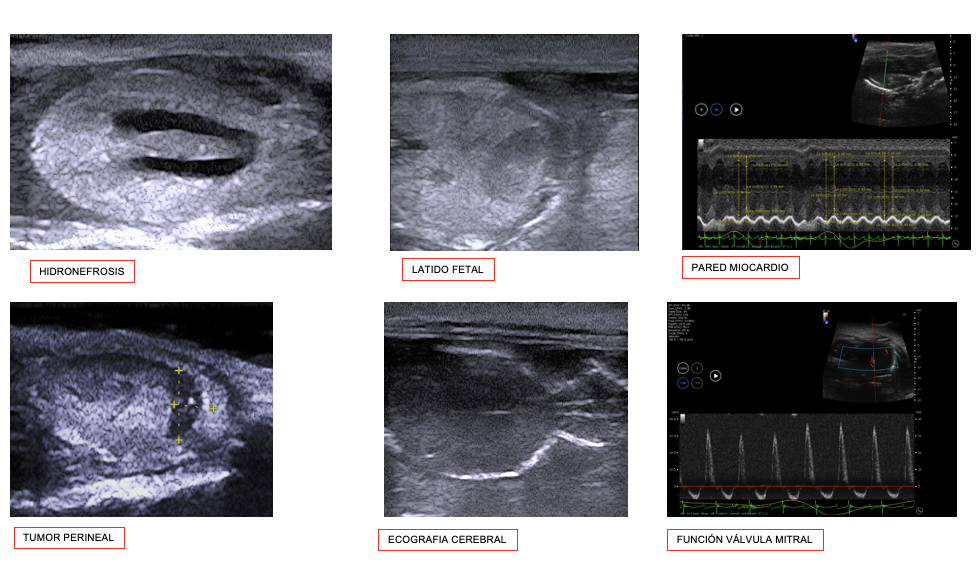

Es tracta d'una tècnica no invasiva en temps real per a estudis cardiovasculars, abdominals, tumorals i embrionaris; també facilita procediments com administracions, puncions o preses de mostres ecoguiades.